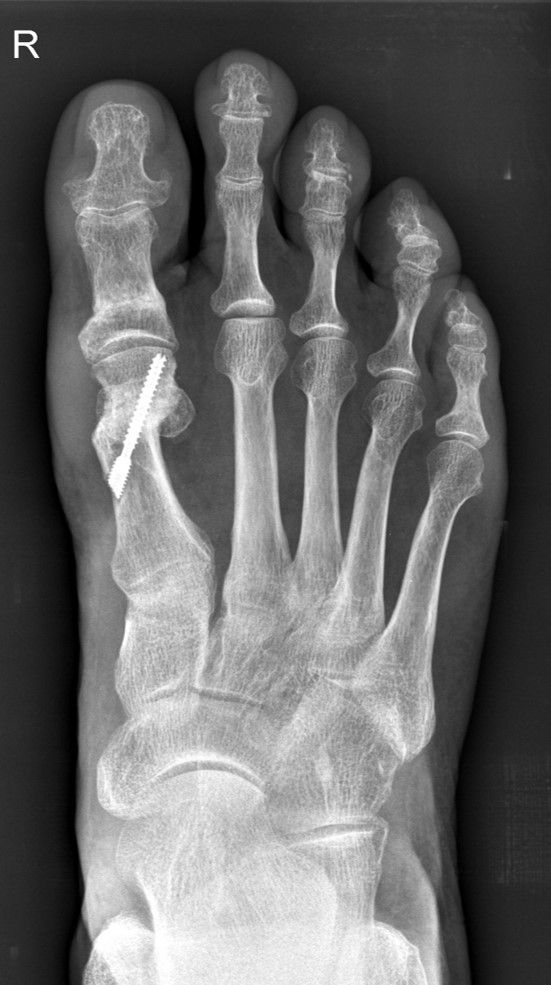

Die Akin-Osteotomie erfolgt in mindestens 50% begleitend zu metatarsalen Osteotomien im Rahmen der Korrektur einer Hallux valgus Deformität 12. Diese gehören zu den am häufigsten durchgeführten orthopädischen Eingriffen. Eine präzise Planung der notwendigen Korrektur unter Berücksichtigung aller Komponenten ist daher unabkömmlich. Dabei sollte eine Valgus-Deformität der Grundphalanx mitbehandelt werden, da diese die Entwicklung eines Rezidivs begünstigt. Die valgische Deformität der Grundphalanx mit veränderten Gelenksflächenwinkeln wird als Hallux valgus interphalangeus bezeichnet (Abb. 1). Dabei können verschiedene Winkel zur Definition der Fehlstellung angegeben werden (Abb. 2) 34. Bei der Beurteilung des Hallux valgus interphalangeus im Rahmen einer Hallux valgus Deformität ist zu beachten, daß häufig eine Hyperpronation der Grundphalanx besteht. Durch diese Malrotation werden die eigentlichen pathoanatomischen Winkel "verprojiziert". Am Röntgenbild erscheinen diese projizierten kleiner als die reellen Winkel. Somit sollte intraoperativ nach einer metatarsalen Osteotomie überprüft werden, ob eine Restfehlstellung im Sinne eines Hallus valgus interphalangeus besteht, da das präoperative Röntgenbild die Fehlstellung nicht immer exakt abbildet.

• Hallux valgus interphalangeus (Abb.1, Abb.2, Abb.3).

• Röntgenaufnahme des Fußes (unter Belastung) in dorsoplantarem und seitlichen Strahlengang (Abb. 3) und präoperative Fotodokumentation.

• Beurteilung des proximalen Gelenkflächenwinkels der Grundphalanx (Proximal Phalangeal Articular Angle, PPAA) des Hallux valgus interphalangeuswinkels (Hallux interphalangeus Angle, HIA) sowie des proximalen zum distalen Gelenksflächenwinkel (Proximal to Distal Phalangeal Articular Angle, PDPAA) 6789 (Abb. 2).